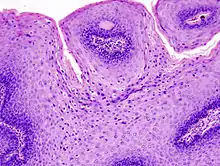

The diagnosis of genital warts is most often made visually, but may require confirmation by biopsy in some cases.[15] Smaller warts may occasionally be confused with molluscum contagiosum.[14] Genital warts, histopathologically, characteristically rise above the skin surface due to enlargement of the dermal papillae, have parakeratosis and the characteristic nuclear changes typical of HPV infections (nuclear enlargement with perinuclear clearing). DNA tests are available for diagnosis of high-risk HPV infections. Because genital warts are caused by low-risk HPV types, DNA tests cannot be used for diagnosis of genital warts or other low-risk HPV infections.[2]